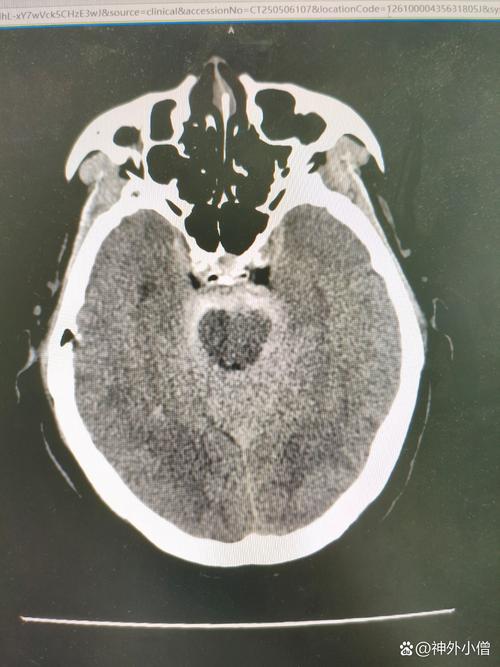

脑内多发缺血及腔梗灶

(图片来源网络,侵删)

1. 脑内:病灶的位置在颅内,也就是我们的大脑里。

2. 多发:不是一个,而是有多个病灶,这表明问题不是偶然发生的,而是有一定程度的普遍性。

3. 缺血及腔梗灶:这是病灶的性质,解释了它们是什么。

• 缺血:指大脑的某个区域供血不足,就像一块田地浇水不够了,导致脑细胞(神经元)功能受损或死亡。

• 腔梗灶:这是“缺血性脑卒中”的一种特殊类型,全称是“腔隙性脑梗死”,它是由大脑深部的一些非常细小的动脉(穿通支)堵塞引起的,因为这些动脉很细,堵塞后坏死的脑组织范围也很小,形成一个像“小洞”或“小腔”一样的病灶,所以叫“腔隙性”梗死。

一句话总结: “脑内多发缺血及腔梗灶”意味着,在大脑的深部区域,存在多个由小血管堵塞或长期供血不足引起的小梗死灶。 它是脑小血管病的一种表现,通常与长期的高血压、糖尿病、高血脂等慢性病有关。